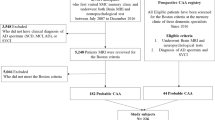

Of the 208 patients included in 2007–2008, 111 completed 7 years follow-up, of whom 26 patients agreed to PET imaging and 13 of these had CSF from 12 months. 12 out of the 26 patients who agreed to PET imaging were diagnosed with CI at 7 years. In total, 80 patients died during the study period, and 17 were lost to follow-up for other reasons. A flow chart is presented in Fig. 1. Characteristics and assessments at baseline and 7 years for the complete study population are presented in Table 1. Characteristics and assessment at baseline, clinical cognitive profile and MRI findings at 1 year in stroke survivors by PET or no PET at 7 years are presented in Table 2. Significantly more patients who agreed to PET had normal cognition and lower CSF T-tau at 12 months follow-up. There were no differences regarding age, stroke subtype or assessments at baseline, or MRI findings at 1 year.

The main characteristics, MRI, 18F-Flut-PET, and cognitive assessment findings are summarized in (see Additional file 1). Among the 26 patients who agreed to PET, five patients had no MRI at 7 years, required in our quantitative assessment method. Four scans were visually classified 18F-Flut(+). 13 patients were diagnosed with CI (mixed or neurodegenerative disease) at 7 years, one with a positive PET scan. Quantitative 18F-Flut-PET SUVr in different cortical regions is presented in Table 3.

Comparing patients according to normal or CI at 7 years, no difference in mean SUVr (SD) was observed (0.57 (0.08) vs 0.60 (0.18), p = 0.54). Eight patients changed from normal cognition at 1 year to CI at 7 years, one of whom was amyloid positive. When comparing cognitive decline to stable cognition during follow-up, no difference in mean SUVr (SD) was observed (0.65 (0.24) vs 0.56 (0.07), p = 0.16). Three of four patients with visually positive PET had normal cognition at 7 years.

Eighty patients died before follow-up, 33 with CSF from 1 year. Logistic regression assessing age-adjusted CSF Aβ42 levels and death, did not demonstrate any significant association (OR 1.0, 95%CI 0.99–1.0). Age-adjusted CSF T-tau was not significantly associated with death (OR 1.0, 95%CI 1.0–1.0).

Our study has several limitations. First our limited sample size, as only 56 patients agreed to lumbar puncture at 1 year and 26 to PET after 7 years. Patients on anticoagulation therapy or those unable to consent, were excluded from lumbar puncture due to ethical considerations. This might bias our findings. After 7 years, due to time consuming examinations and long travel distances between hospitals, only highly motivated patients, and more of those with normal cognition at 1 year, agreed to PET, making our findings less generalizable. The strength of our study is the long-term follow-up with the same team of nurses and physicians, and measurement of amyloid at two time points. As far as we know, this is the first study to offer PET examination 7 years post-stroke, and by that adding important knowledge to amyloid evaluation post-stroke.